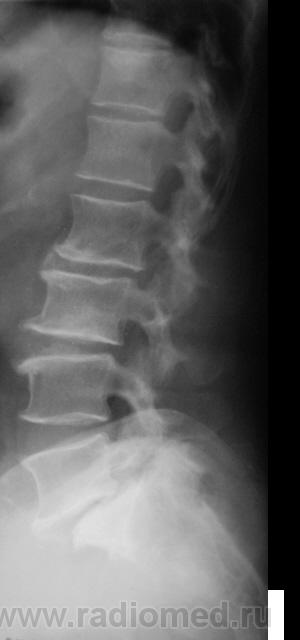

Спондилолистез L5-S1 - истинный, поэтому природа сама набедокуривши, сама и оберегает. Трудно представить безсимптомное течение, если бы это было последствием травмы. Очень рад, что Андрей Юрьевич приводит выдержки из Рейнберга. Судя по желтизне страниц - это первое издание.

По данному случаю:на мой взгляд, он является примером того, что попытки обяснить клинику(страдания пациента) только изменениями на R-граммах несостоятельны (если бы, у пациентки были жалобы,скажем на боли в области поясницы, сделали бы вывод-"что вы хотите?!-деформирующий спондилёз, да ещё спондилолистез- из-за этого и болит"). Думаю, многие сталкивались такими направлениями: "Направляеться на R-графию пояснично-крестцового отдела позвоночника.D.S.:Исключить остеохондроз ".

А во сколько лет человек заимел все -озы? И спондилолиз с листезом 2 ст?